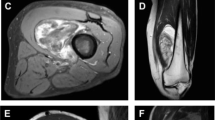

Lipoblastoma with intraspinal extension in a 3-year-old girl presenting with dyspnea. a Axial contrast-enhanced CT of the neck shows intracanalicular extension (arrow) of this complex fat-containing mass. b Coronal T1-weighted MR image demonstrated leftward mediastinal shift with tracheal deviation (not pictured) and shows transcompartmental extension of a fat-containing lesion through the thoracic inlet (arrow) and intraspinal extension (arrowhead). Pathology confirmed lipoblastoma

Specific findings of compartmental invasion included transfascial involvement and muscle infiltration (n=14, 25%, Fig. 4); neurovascular encasement (n=4, 7%, Fig. 5); intraspinal extension (n=3, 5%, Fig. 6); mediastinal and tracheal displacement (n=1, 2%, Fig. 6); rib remodeling (n=1, 2%); and bowel encasement (n=1, 2%), which required partial bowel resection. Of lesions located within the paraspinal soft tissues near the vertebral column (n=8, Figs. 6 and 7), 38% (n=3) entered the neural foramen or spinal canal (Fig. 6).

While lipoblastoma is a benign tumor, several cases exhibited locally aggressive-appearing behavior in this case series with compartmental invasion. Lipoblastoma can extend through fascial planes and into skeletal muscle (Fig. 4), as seen in 20% of cases in this series and consistent with prior reports [13]. Previous reports have deemed such intraspinal extension rare, although a few cases exist in the lipoblastoma literature [18,19,20,21]. Of the eight cases of deep paraspinal lipoblastoma in this study, three (38%) demonstrated intraspinal extension (Fig. 6). These observations suggest that when a lipoblastoma is paraspinal in location and demonstrates diffuse infiltration, intraspinal involvement should be carefully considered and inspected for on MRI, especially because these deeper components are difficult to resect completely without morbidity and likely portend higher recurrence risk.

Lipoblastoma arising within the neck, chest and abdomen can have significant growth, resulting in clinically significant mass effect. Mediastinal and neck lesions can result in respiratory compromise, and dyspnea was common in children with lipoblastoma in these locations in our study, with tracheal deviation in one case (Fig. 6), as previously reported particularly in infants [22, 23]. We also observed four cases of neurovascular encasement in the neck and superior mediastinum where tumor surrounded major vessels and nerves. A few cases of such neurovascular encasement have been reported in which lipoblastoma surrounded but did not invade vessel walls [23]. One such case in this study precluded complete resection of an intra-abdominal mass because of encasement of the superior mesenteric artery (Fig. 5).